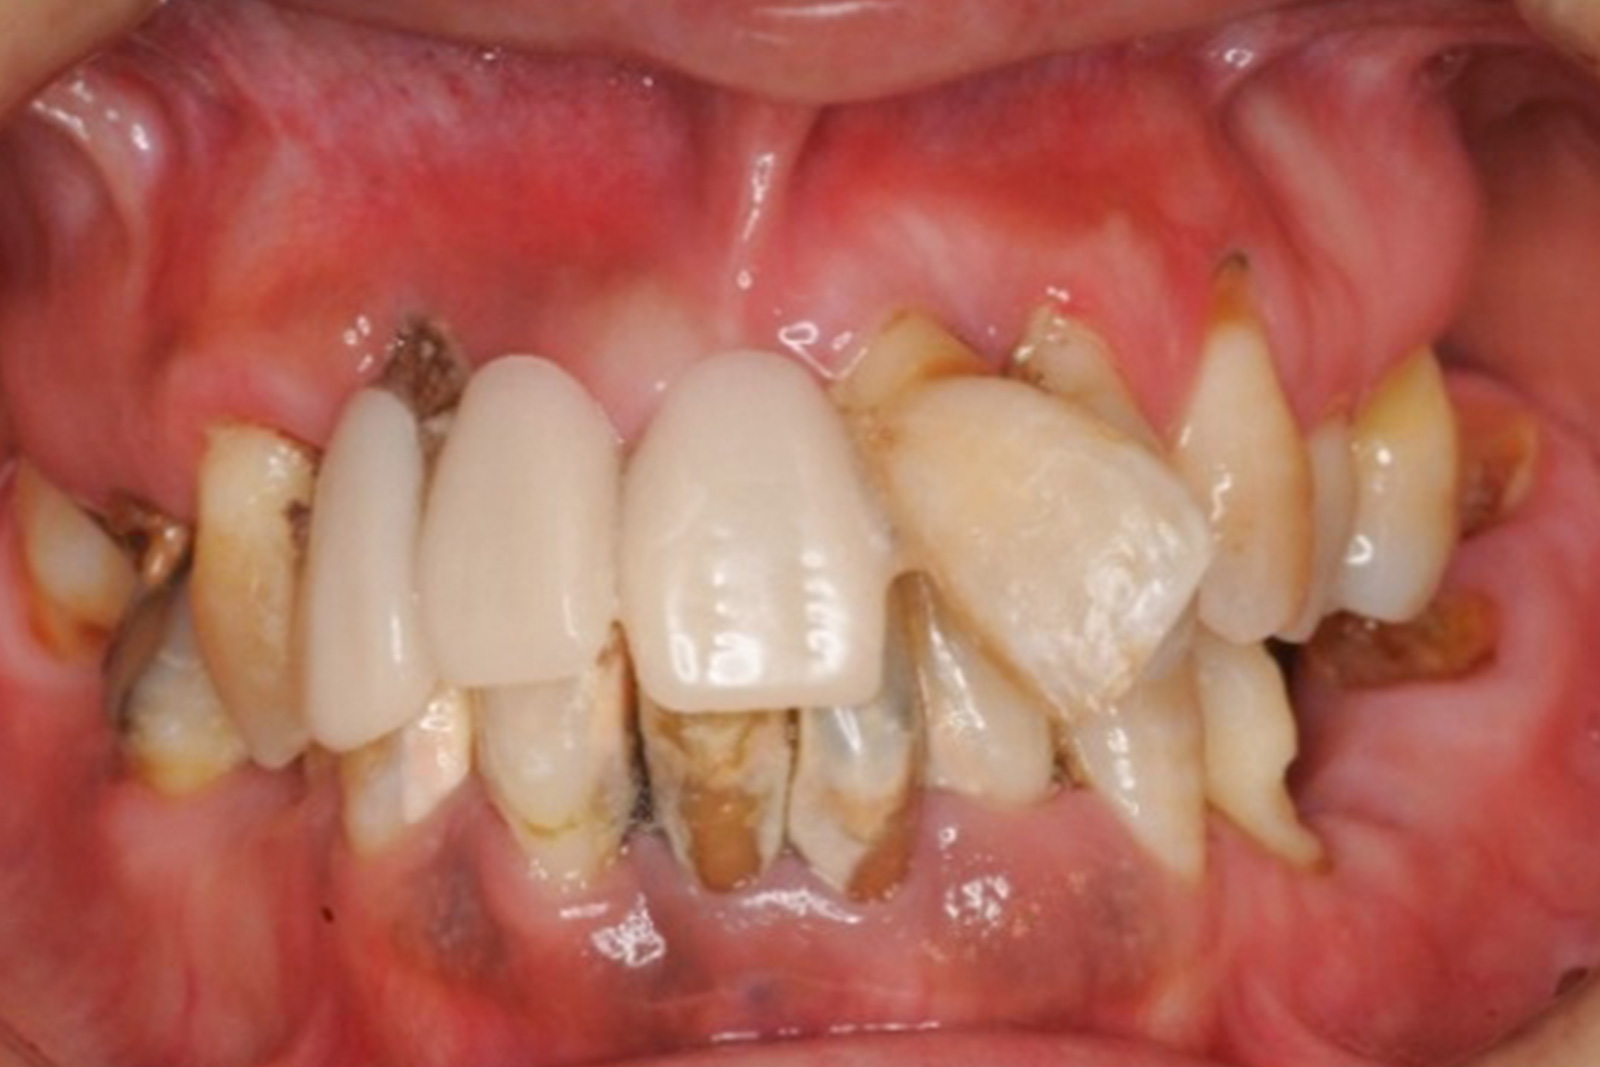

虫歯や歯周病を治療せずに放置していると、写真のように歯がボロボロの状態になってしまいます。

ここまで悪化すると、「もう、どうしようもない」と諦めてしまう方もいらっしゃいます。

ですが、決して諦めないでください。

歯科医療の進歩によって、ボロボロになった歯でも、歯の修復や機能の回復が可能になってきました。

もちろん、患者さんの自覚や努力も必要ですが、さまざまな治療によって、残った歯を守り自分の歯を使い続けることも可能です。